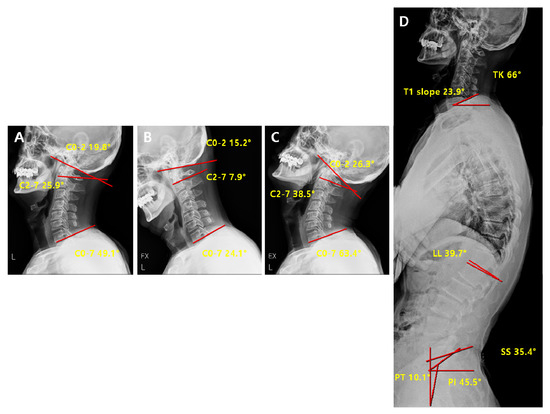

| Parameters | Definition |

|---|---|

| C2-7 Cobb angle | The intersection angle between the line perpendicular to the line parallel to the C2 lower endplate and the line perpendicular to the line parallel to the C7 lower endplate |

| C0-2 Cobb angle | The occipito-cervical angle, which is the intersection angle between the McGregor line and the line parallel to the C2 lower endplate and is used to evaluate the curvature of the upper cervical spine |

| C0-7 Cobb angle | The intersection angle between the McGregor line and the line parallel to the C7 lower endplate |

| C0-2/C0-7 | The value of C0-2 Cobb angle divided by C0-7 Cobb angle |

| C2-7/C0-7 | The value of C2-7 Cobb angle divided by C0-7 Cobb angle |

| T1 slope | The intersection angle between the tangent line and the upper plate of the T1 vertebral body |

| SS (Sacral Slope) | The angle formed by a line drawn along the endplate of the sacrum and a horizontal reference line |

| PT (Pelvic Tilt) | The angle formed by a line drawn from the midpoint of the sacral endplate to the center of the bicoxofemoral axis and a vertical and a vertical plumb line |

| PI (Pelvic incidence) | The angle formed by two vectors: (1) The line joining the bicoxo-femoral axis to the center of the sacral end plate and (2) A line perpendicular to the sacral endplate |